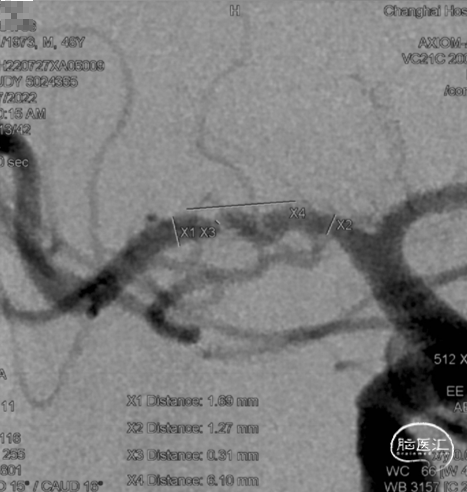

➤术前DSA检查

右侧大脑中动脉重度狭窄,左侧前循环未见明显异常。

后循环未见明显异常。

病变部位: 右侧大脑中动脉M1段重度狭窄;狭窄率: 75.6%;狭窄长度: 6.10mm;参考远端血管直径: 1.27mm。